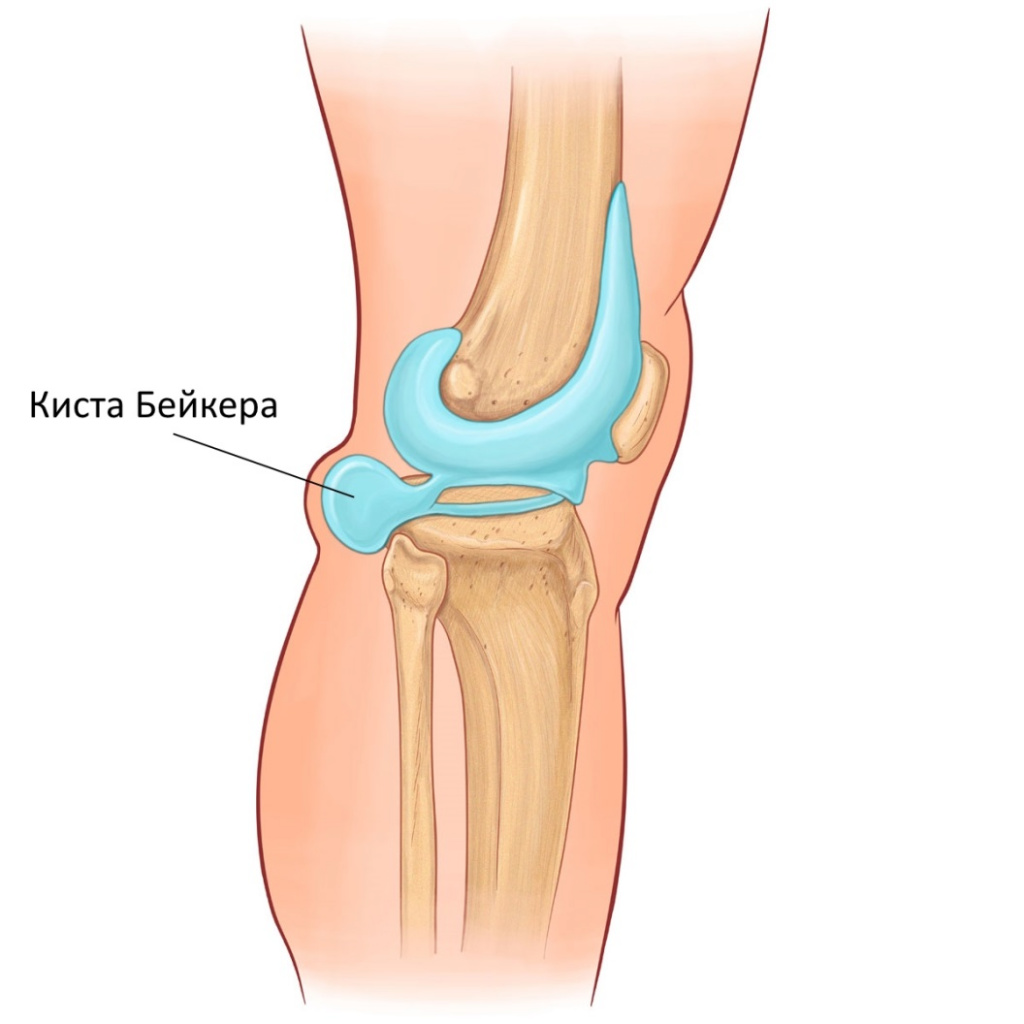

Заболевания и медицинские снимки: Жидкость в коленной чашечке